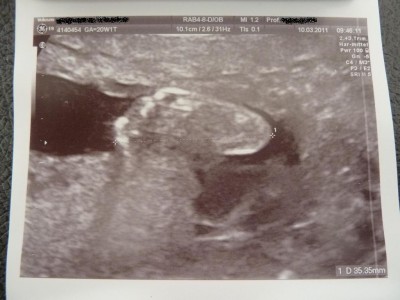

@all: die heute Feindiagnostik war zum Glück sehr angenehm.

Der kleine Mann scheint eine recht vergnügliche Behausung zu haben. Er „sitzt“ nunmehr in meinem Bauch und lässt sich durch die Gegend schaukeln. Beim Termin vor eineinhalb Wochen lag er ja noch in Schädellage. Ab und an „saß“ er im Schneidersitz drinnen und war recht gemütlich.

Der Hammer war, dass sie beim Schallen des Köpfchens den Ultraschallkopf kurz unter meinen Rippen gehalten hat. Also ganz weit oben. So riesig hatte ich mir das alles gar nicht vorgestellt.

Jedenfalls waren keinerlei Auffälligkeiten zu entdecken.

Ausgehend von der Femurlänge hat der kleine Mann eine Gesamtlänge von stolzen 22 cm. Wahnsinn, oder???

Auch die Durchblutung war vollkommen in Ordnung und sie hat dafür nur einen Versuch pro Seite und pro Seit maximal 20 Sekunden für die Messung gebraucht. War nicht schwierig. Was mich extrem erleichtert hat.

Ansonsten war der kleine Mann wie immer Fotoscheu. Er hat IMMER die Händchen vor dem Gesicht gehabt. Insofern hatten wir nicht viel vom kurzen Umschalten auf 3D. Aber süße Patschehändchen hat er, das wissen wir jetzt genau.

Bin sehr froh und erleichtert. Man hat ja doch immer ein wenig Schiss, dass doch irgendwas sein könnte.

Mein Menne war auch ganz ergriffen und stolz und froh.

Anbei noch 2 Bildchen. Auf dem einen ist das Profil, nicht sehr gelungen aufgrund der Schwierigkeiten, die der Kleine beim Fotografieren macht. Auf dem anderen ist ein Füßchen zu sehen. Das Füßchen ist immerhin schon 3,5 cm lang –Wahnsinn, oder??????????

Ich schick euch allen ganz liebe Grüße!!!